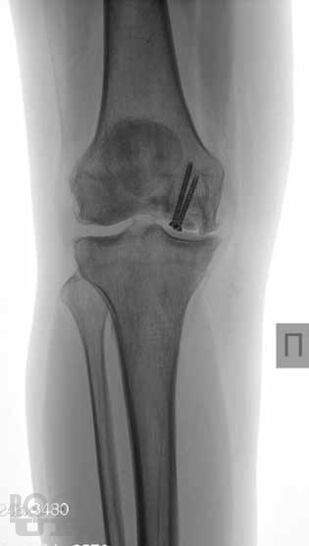

В основу книги положен многолетний опыт исследований коленного сустава в многопрофильной клинике с развитой ревматологической и ортопедической службами. Авторами приводится непредвзятое освещение возможностей современных методов лучевой диагностики патологии коленного сустава с адекватным позиционированием ультразвуковых исследований на различных этапах оказания медицинской помощи. Проанализирован опыт отечественных и зарубежных авторов, суммированы результаты многочисленных оригинальных собственных исследований. Подробно освещены особенности ультразвукового исследования широкого спектра патологических состояний и заболеваний травматического, воспалительного генеза, встречающихся у молодых и пожилых пациентов.

В книге представлен большой иллюстративный материал. Подробно изложена топографическая и ультразвуковая анатомия коленного сустава, рассмотрены технические особенности проведения исследования, варианты визуализации многочисленных патологических изменений.